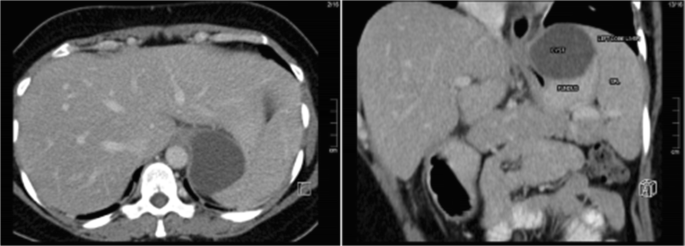

Laparoscopic Sleeve Gastrectomy for Oesophago-gastric Junction